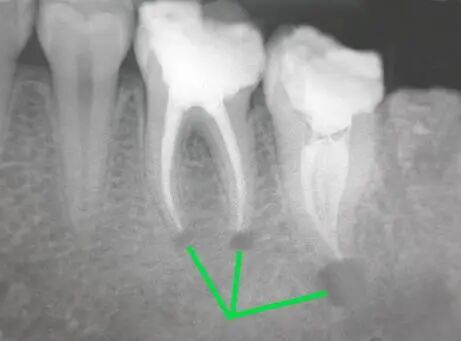

暗的部位说明龋齿已经非常严重了!

下面这个是接近牙髓了。